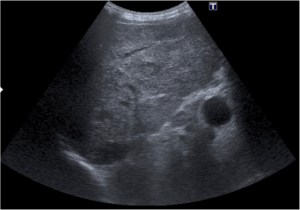

- Ecografía: es una herramienta accesible y se puede usar para una primera valoración de la hematuria. Sin embargo, tiene una sensibilidad del 80% y es poco útil para el diagnóstico de tumores del tracto superior.

Tras el tratamiento de la recidiva y nefrostomía para la hidroureteronefrosis, vuelve acudir al hospital a los 9 meses por episodio de dolor en FD y malestar general. Se realiza una ecografía de urgencias.

Se realiza nueva TC bifásico abdominopélvio y Uro TC.